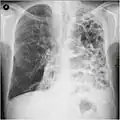

A chest X-ray is not useful to establish a diagnosis of COPD, but it is of use in either excluding other conditions or including comorbidities such as pulmonary fibrosis and bronchiectasis. Characteristic signs of COPD on X-ray include hyperinflation (shown by a flattened diaphragm and an increased retrosternal air space) and lung hyperlucency.[5] A saber-sheath trachea may also be shown that is indicative of COPD.[111]